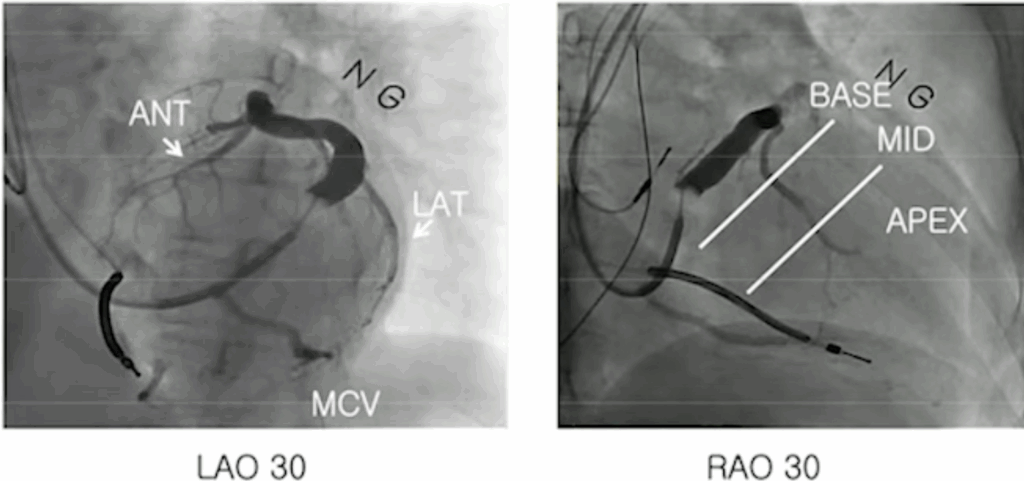

The first thing to visualize carefully is the anatomy of the coronary sinus in RAO 30° and LAO 30° (ideally 40°).

In the RAO view, the atrium appears on the left side of the screen and the ventricle on the right.

This projection helps determine whether a structure is basal, mid, or apical.

In the LAO view, you visualize the two “discs” of the right ventricle, with the right-sided structures on the left of the screen and the left-sided structures on the right.

After positioning the RV lead first, the next step is to cannulate the coronary sinus and inject contrast in both LAO and RAO views to identify the optimal target vein for placing the LV lead.